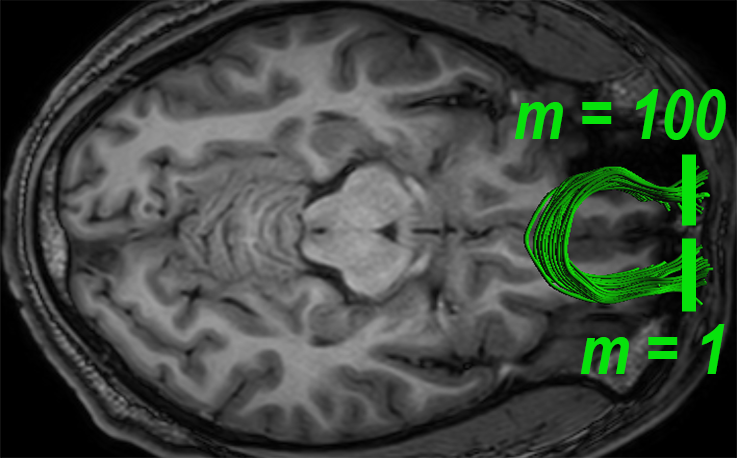

A fiber bundle can be thought of as a set of similar trajectories with a common origin and destination, along which water molecules are diffused [13]. In the spirit of this notion, we define a local measure for quantifying the fiber-flux of through a given plane , with normal at point , i.e.,

| (1) |

where is the number of intersected fibers, is the set of intersection points between the plane and the fiber bundle, and are the tangents of the fibers at those points. We call the fiber-flux density (FFD) of bundle at point . The plane is oriented such that the fiber-flux is maximized, i.e., . We use an iterative approach to solve this maximization problem in the spirit of [27]. We further introduce diffusivity properties into our model by extending the FFD measure. Let define a diffusivity scalar of choice (FA, MD, AD, or RD), associated with the point . We define the fiber-flux diffusion density (FFDD) as follows:

| (2) |

In practice, we refer to the FFDD as a vector to account for the local orientation of the fiber bundle. Note that the set of four FFDD descriptors (each assigned with a different diffusivity measure) couples diffusion measures with local geometrical features of the bundle. For example, local differences in orientation are taken into account, and regions with “incoherent” fiber orientations are “punished” by having lower FFDD values.

2.2 Along Tract Profiles

We calculate the mean fiber of the bundle , where is its arc-length parameter, based on Fourier descriptor [5]. According to this method, individual streamline fibers are represented by the coefficients of cosine series expansions, which are computed from tractography data using least squares estimation. The mean fiber is then optimally obtained by averaging the representation coefficients and applying the inverse transformation. The locations of the planar cross-sections along the bundle are determined by equidistant sampling points along the mean fiber . Tract-profiles are obtained by applying the FFDD descriptors along the tract, over these points.